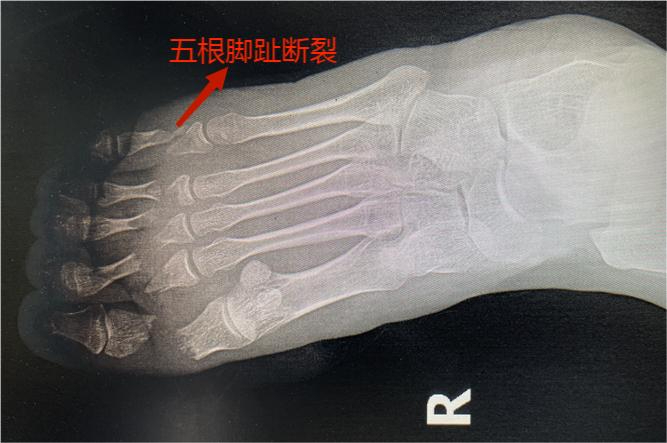

女子5根腳趾被700多公斤的重物砸斷,晉城大醫(yī)院鏖戰(zhàn)6個(gè)小時(shí)全部接回!

8月底,二十多歲的小薇(化名)工作時(shí),被700多公斤的重物砸傷右足,5個(gè)腳趾被砸斷,緊急來(lái)到晉城大醫(yī)院。面對(duì)可能失去5根腳趾的風(fēng)險(xiǎn),晉城大醫(yī)院手足及顯微外科是如何竭盡全力保住腳趾的?我們一起去看看。

二十多歲的小薇,不慎被700多公斤的重物砸傷右腳,疼痛不止,同事立即將她送往晉城大醫(yī)院。醫(yī)生立即進(jìn)行查體和相關(guān)檢查發(fā)現(xiàn),即便是工作時(shí)穿了鐵鞋保護(hù),巨大的重力仍將1-5趾的趾骨砸斷,5個(gè)腳趾綿軟無(wú)力,比骨折更嚴(yán)重的是5根腳趾所有的血管全部損傷,末梢冰涼,完全沒(méi)有血液循環(huán)。